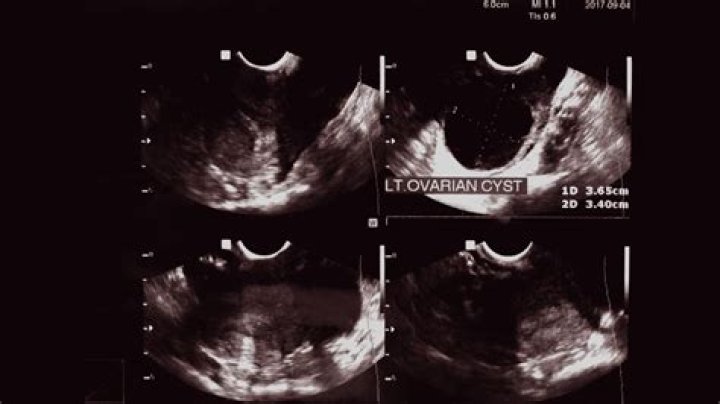

When women experience pelvic pain and abnormal bleeding, doctors can use ultrasound imaging to help find the cause. These scans often also find growths in the ovaries. The most common type, called a simple cyst, isn't usually harmful.

HOW OFTEN SHOULD IMAGING BE REPEATED? In premenopausal women, most simple (thin-walled) ovarian cysts less than 5 cm in maximum diameter resolve in 2 to 3 menstrual cycles and do not require further intervention. Larger cysts (5–7 cm in diameter) should be followed with ultrasonography yearly.

Ovarian cysts can sometimes be detected during a pelvic examination, although an imaging test, usually a pelvic ultrasound, is necessary to confirm the diagnosis. Computed tomography (CT) scan or magnetic resonance imaging (MRI) are also sometimes used, but less commonly.

If your gynecologist suspects that your symptoms could be due to ovarian cysts the best way to diagnose these cysts is through a pelvic exam or by performing an ultrasound. The ultrasound will allow your doctor to examine the abdomen in detail to see if cysts are present.

2. Ultrasound. An ultrasound can pinpoint the location, size, and makeup of ovarian cysts. ...